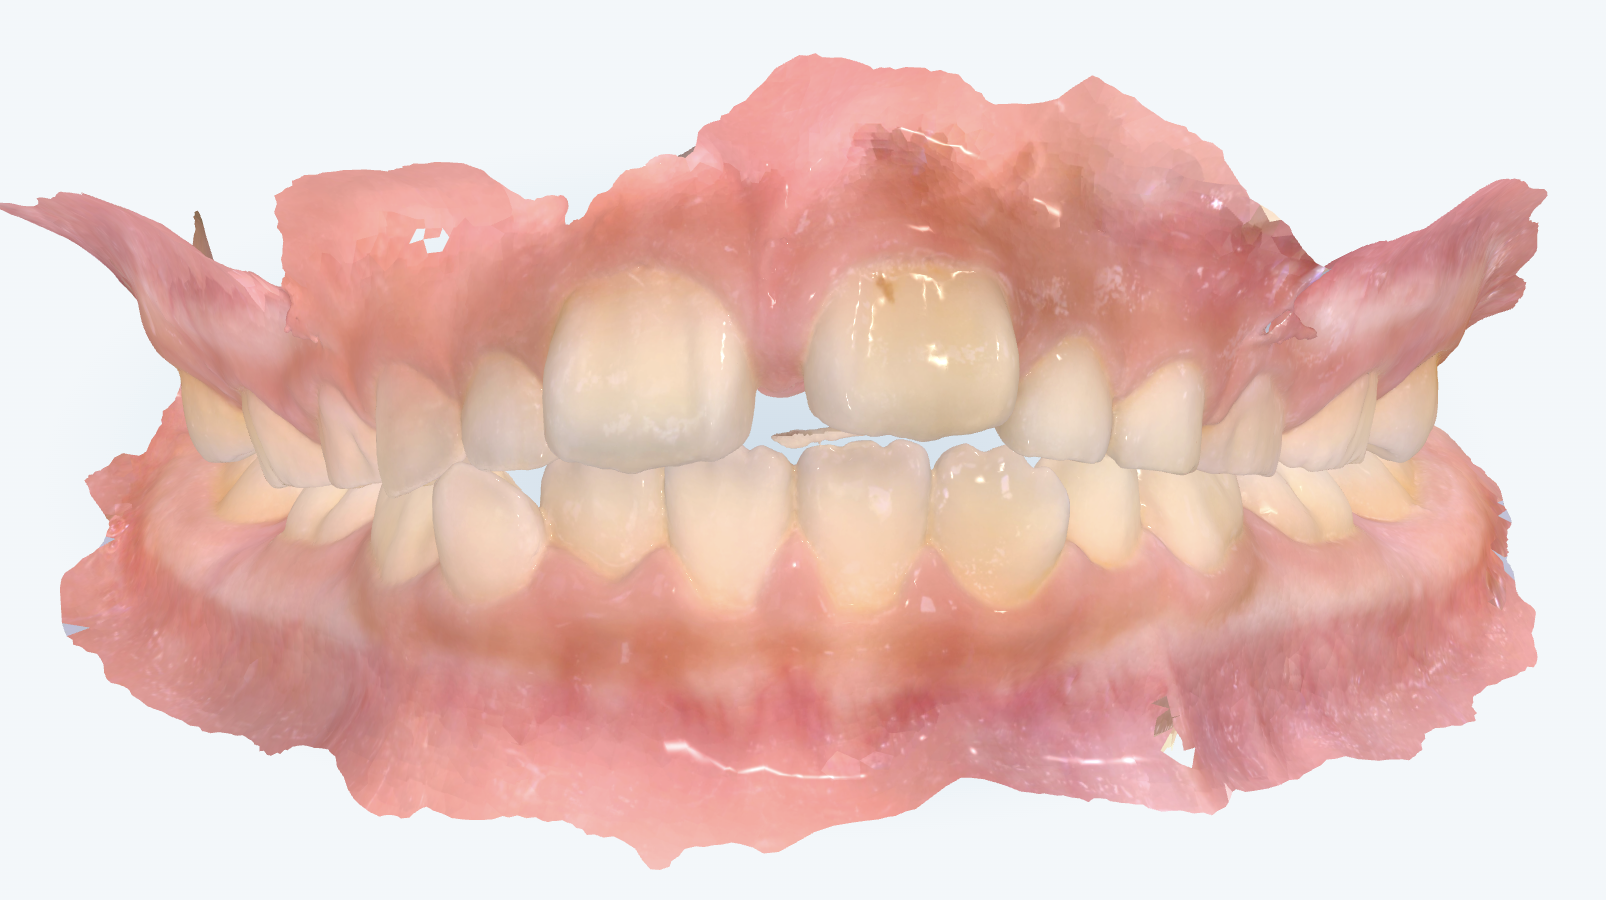

初診時の画像診断

出っ歯傾向が見られました。上の歯並びはV字状の歯列の形でした。

上の前歯はすきっ歯(正中離開)になっていました。